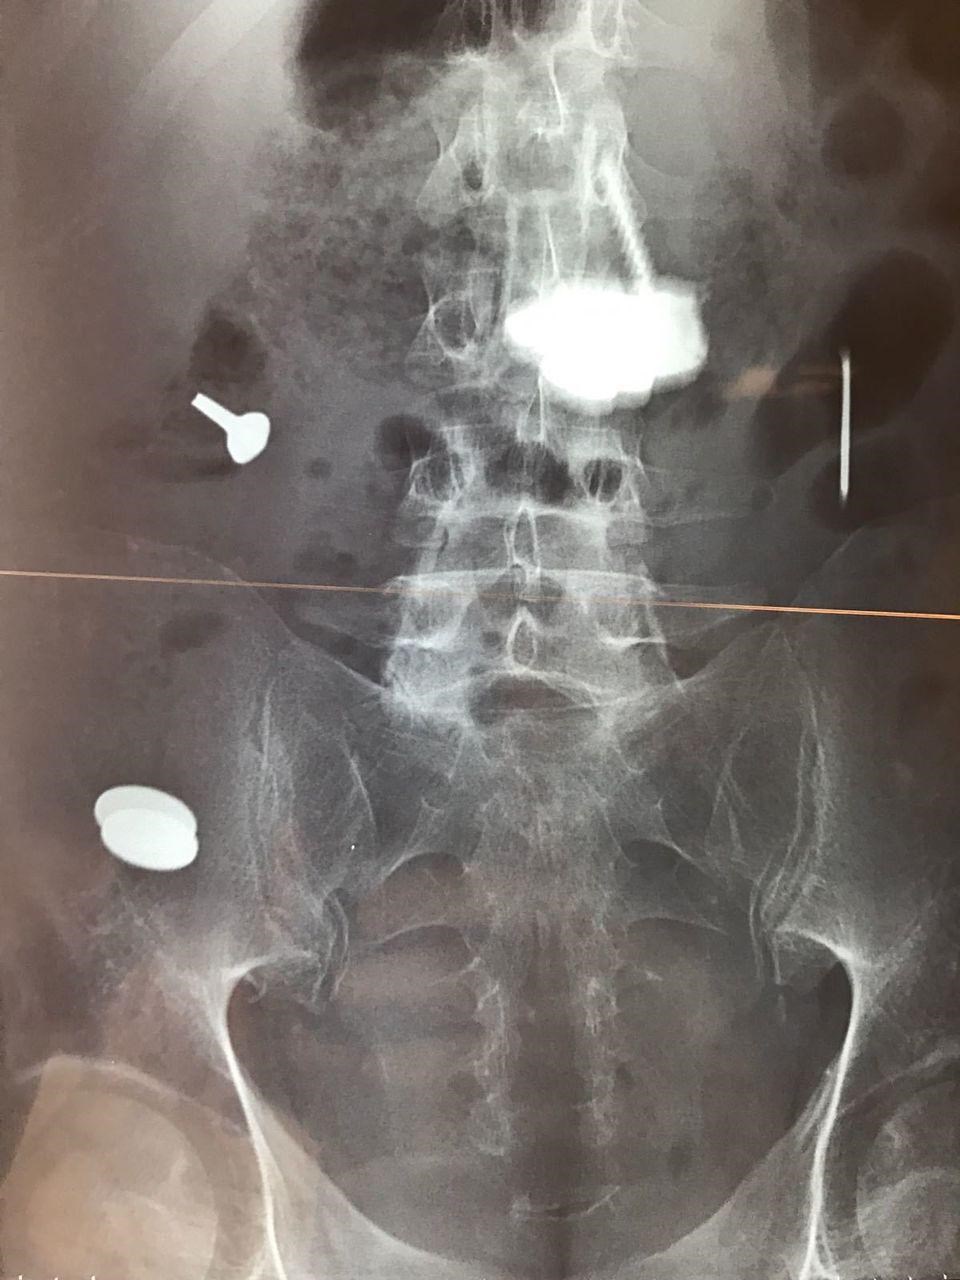

Περισσότερα από 100 κομμάτια μετάλλων διαφόρων σχημάτων και μεγεθών, τα οποία είχε καταπιεί λόγω ψύχωσης, αφαίρεσαν από το στομάχι ενός άνδρα, Γάλλοι χειρουργοί.

Σταδιακά ορισμένα μεταλλικά αντικείμενα, που είχαν χωνευθεί μόνο εν μέρει ή καθόλου, είχαν σχηματίσει ενιαίες μεταλλικές μάζες μέσα στο στομάχι του, τόσο μεγάλες που είχαν φράξει τον πυλωρό, το στόμιο που συνδέει το στομάχι με το λεπτό έντερο, πράγμα που εμπόδιζε το άδειασμα του στομαχιού του από το περιεχόμενό του.

Ο άνδρας είχε πάει πέντε φορές στα επείγοντα περιστατικά των νοσοκομείων σε διάστημα πέντε ετών, παραπονούμενος για στομαχόπονους, ναυτίες και εμετούς με αίμα. Σε τέσσερις περιπτώσεις οι γιατροί χρειάσθηκε να τον εγχειρίσουν για να αφαιρέσουν μεταλλικές μάζες από το στομάχι του, κάτι που δεν ήταν δυνατό να γίνει μόνο με το ενδοσκόπιο.